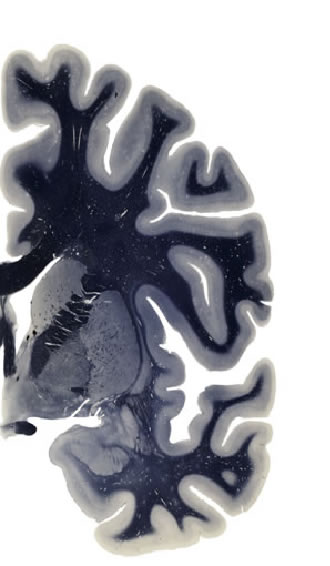

Hi-Resolution Sections · Cells (Nissl Staining) · Virtual Microscopy

Frontal sections (Nissl) from the Atlas Brain:

Slice ID:

r3-1373

Plate NR:

ca 23

Position:

0,72 mm